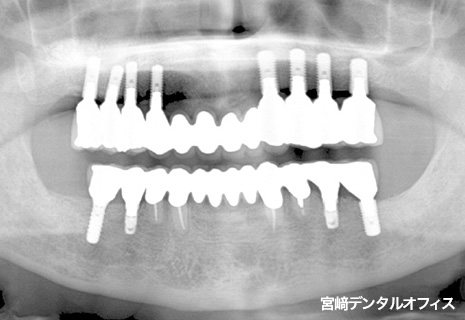

全顎的治療

術前

術後

インプラント治療